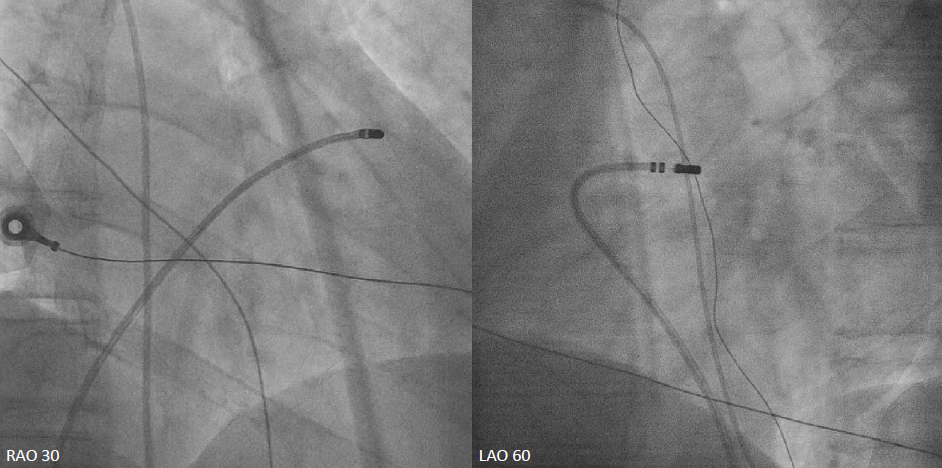

The left coronary artery was engaged with an XB 3.5¡¿6 Fr guide catheter. Using a Fielder FC guidewire with a Fine-Cross microcatheter, the distal LAD was successfully accessed. Pre-dilation with a 1.5¡¿20 mm balloon demonstrated residual stenosis with poor flow. Further dilation with a 2.0¡¿15 mm balloon improved flow. Intravascular ultrasound (IVUS) revealed intramural hematoma (IMH) in the proximal-to-mid LAD. A drug-eluting stent (BMX6 2.75¡¿33 mm) was deployed from the proximal LAD (distal to the first diagonal branch) to the mid LAD, followed by proximal post-stent dilation with a 4.0¡¿12 mm non-compliant balloon at 4-16 atmospheres. Post-deployment IVUS confirmed adequate stent expansion without malapposition. Final coronary angiography demonstrated TIMI grade 3 flow.